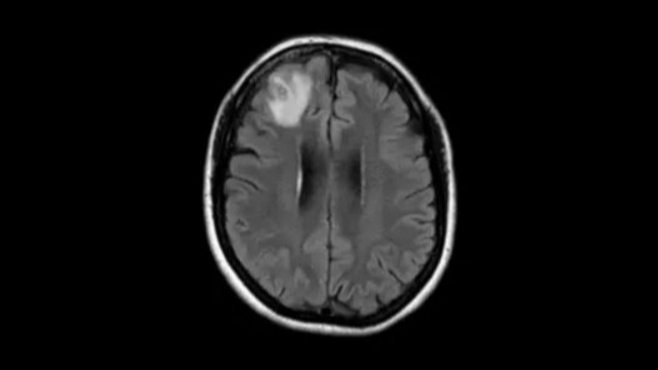

A씨는 최근 태국·일본·하와이를 3주간 여행한 뒤 귀국 후 심각한 건강 이상을 호소했다. 처음에는 단순 피로감으로 여겼으나, 발부터 시작된 타는 듯한 통증이 다리와 팔로 퍼졌다. 초기 검사에서는 특이점이 발견되지 않았지만 두통까지 동반되며 증상이 악화됐다.

매사추세츠 종합병원 카를로스 카스티요 박사 치료팀은 정밀검사 결과 ‘광동주혈선충증’ 감염을 확인했다. A씨의 룸메이트는 “그가 몇 시간 동안 방향 감각을 잃었다”고 전했다.

광동주혈선충증은 동남아시아를 비롯해 남태평양의 섬 등 환태평양 지역 일대에 퍼져 있다. 증상은 오염된 음식을 먹은 후 몇 시간 또는 며칠 후 메스꺼움, 구토, 복통으로 시작된다. 이후 두통, 발열, 근육통, 피로, 불면증, 신경학적 증상이 나타날 수 있으며 목이 뻣뻣하고 통증이 있을 수 있다. 또한 피부가 따끔거리거나 타는 듯한 느낌, 장이나 방광 장애, 발작 등이 나타날 수 있다.